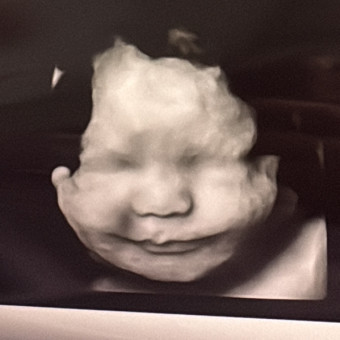

Hayden's Registry 🩵

KateLynne & Chris Thresher

Winterville, NC

February 4, 2026

We are excited to meet our baby boy early next year! Although we still have some of Sophia's things, we got rid of a lot of the new born items and don't have much of anything "boy" wise. All items are greatly appreciated!